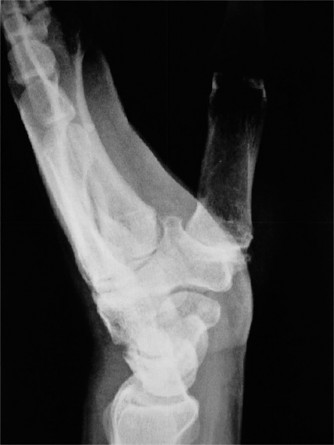

CASE 21 Following an intense game of football, a player is brought to you with …